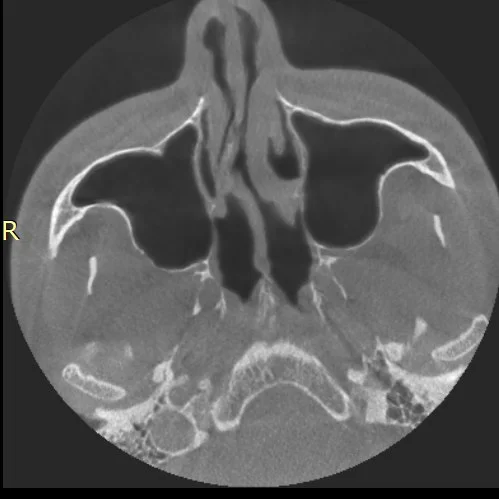

А что тут рассказывать?

КТ надо делать.

А там вооот такая кривая перегородка в носу. Правая ноздря почти перекрыта.

Кстати теперь я не понаслышке знаю выражение "кровь из глаз".

Делал операцию ,минимально лучше стало ,ну у тебя там конкретный такой изгиб надеюсь поможет )